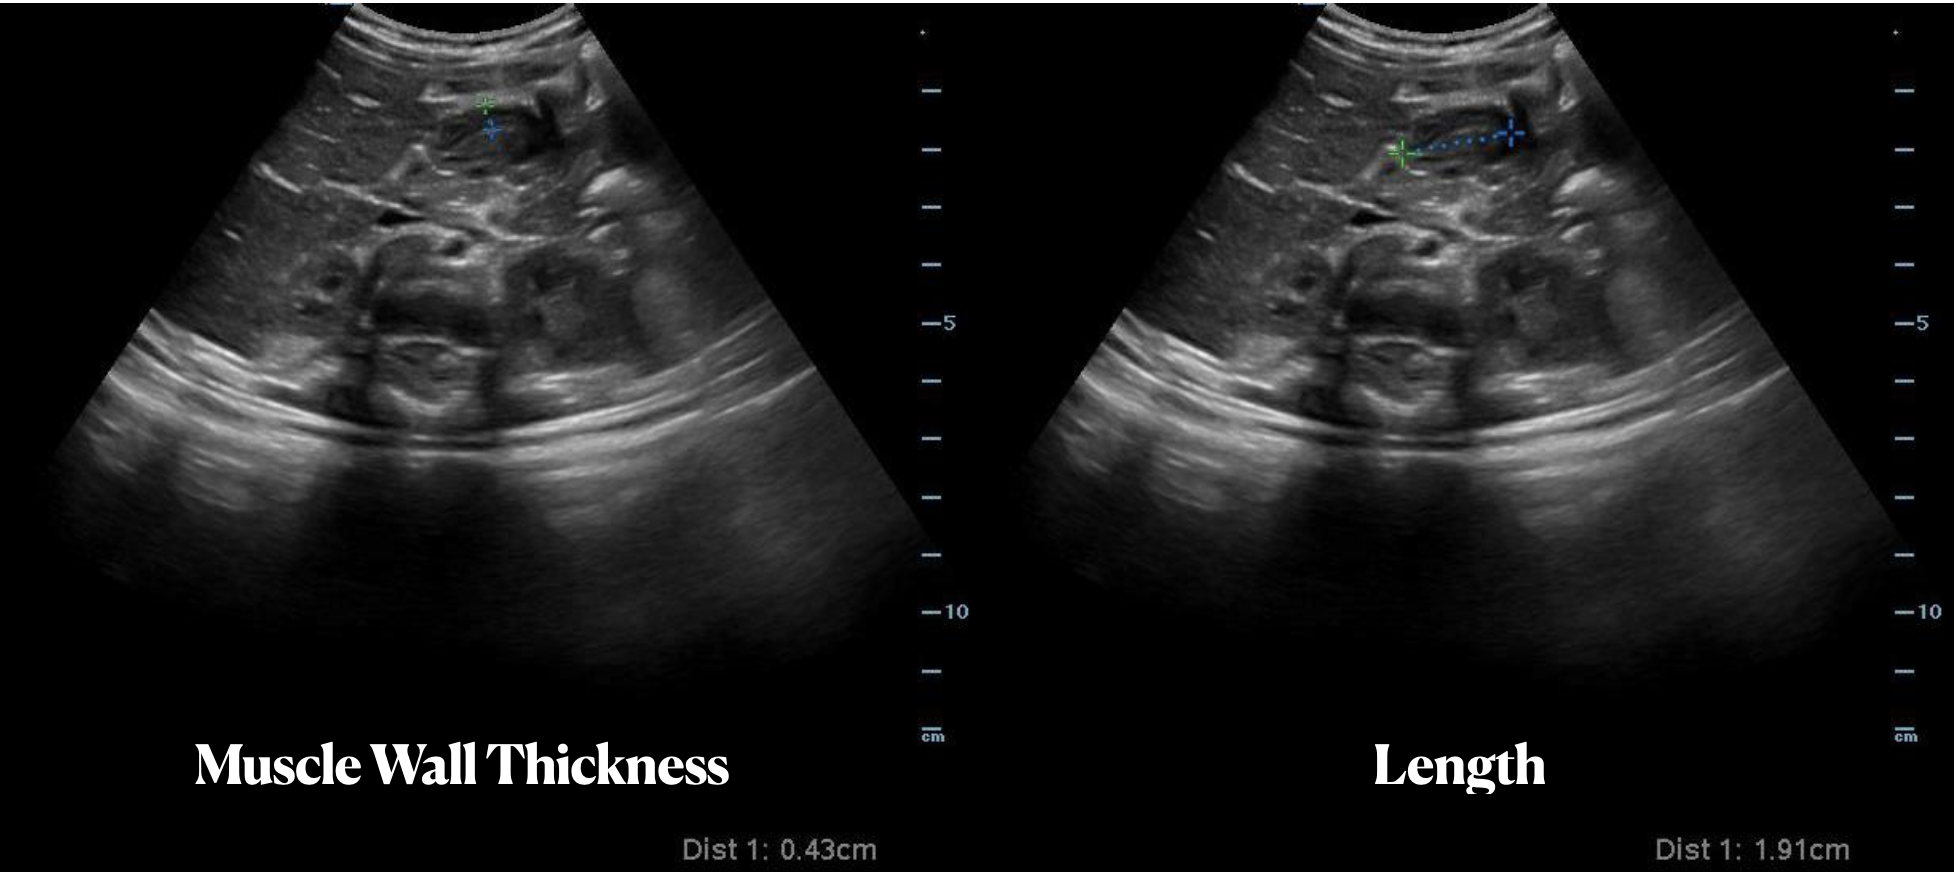

Measurements in Pyloric Stenosis

A 5 week old female previously healthy presents with 1 day of projectile vomiting. A bedside ultrasound was performed demonstrating muscle wall thickness of 4.3 mm (> 3 mm is abnormal) and a length of length of 19 mm (abnormal is >15 mm) consistent with a diagnosis of hypertrophic pyloric stenosis.

Paul Khalil, MD @Khalil3Paul

Assistant PEM POCUS Director at University of Louisville/Norton Children’s